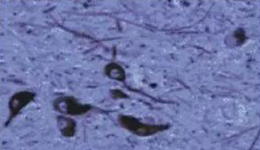

PDµÄ²¡Àí¸Ä±äÖ÷ҪλÓÚºÚÖÊ£¬£¬£¬£¬£¬²¢ÇÒ±äÐÔ¡¢ÍÑÂäµÄϸ°ûÖ÷ÒªÊÇÖÂÃÜ´øµÄ¶à°Í°·ÄÜϸ°û¡£¡£¡£¡£¡£±ðµÄ£¬£¬£¬£¬£¬À¶°ßºË¡¢ÃÔ×ßÉñ¾­±³ºË¡¢ÖзìºËµÈÄÔ¸ÉÖк¬ÓÐÉ«ËØµÄÉñ¾­Ï¸°ûȺҲÓÐÏÔ×ŵıäÐÔ£¬£¬£¬£¬£¬»ùµ×½ÚºËÒ²ÓÐÏÔ×ŵIJ¡±ä¡£¡£¡£¡£¡£PDµÄÁíÒ»¸ö²¡ÀíÌØµãÊDZäÐÔÇøÊ£ÓàµÄÉñ¾­Ôª°û½¬ÄÚµÄLewyСÌ壬£¬£¬£¬£¬µ«LewyСÌåµÄÒâÒåδÃ÷¡£¡£¡£¡£¡£×îеÄÑо¿·¢Ã÷¦Á-Í»´¥ºËÂѰ×Í»±äÔÚLewyСÌåÓëPDµÄ²¡ÒòÓйØ£¬£¬£¬£¬£¬µ«½üÄêÀ´µÄÑо¿·¢Ã÷LewyСÌåÊÇϸ°ûÕý³£ÒòËØ-Éñ¾­ÔªË¿×é³É¡£¡£¡£¡£¡£LewyСÌå²»ÊÇPDÌØÓУ¬£¬£¬£¬£¬LewyÌå³Õ´ôÒ²¿ÉÒÔ¿´µ½¡£¡£¡£¡£¡£

• Õý·²ÈË£ººÚÖÊÉñ¾­Ôª±£´æ

Õý·²ÈË£ººÚÖÊÉñ¾­Ôª±£´æ

• PD»¼ÕߺÚÖÊÉñ¾­ÔªÉ¥Ê§

PD»¼ÕߺÚÖÊÉñ¾­ÔªÉ¥Ê§